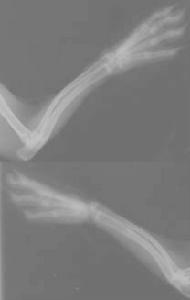

X線表現檢查。

成骨不全骨質疏鬆和骨的脆性增加。

本病是一種先天遺傳性疾病,應預防骨折,對患兒採取保護措施,避免造成骨折的傷害,,訓練柔韌性、耐力和力量,鼓勵各種形式的安全主動運動,從而在最大程度上增加骨量、增強肌肉力量,促進獨立生活功能,甚至勝任一些力所能及的工作,一直到骨折趨減少為止,同時要注意防止長期臥床的併發症,護理患兒,佩戴支具以保護並預防肢體彎曲畸形。